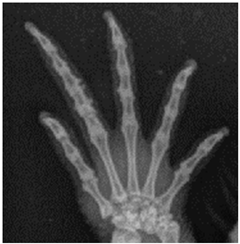

![]() | Left phalanx of the forelimb: identifiability of the joint contours of the interphalangeal joints: visualization and demarcation of the bone contour to the joint space, demarcation to the surrounding tissue. |